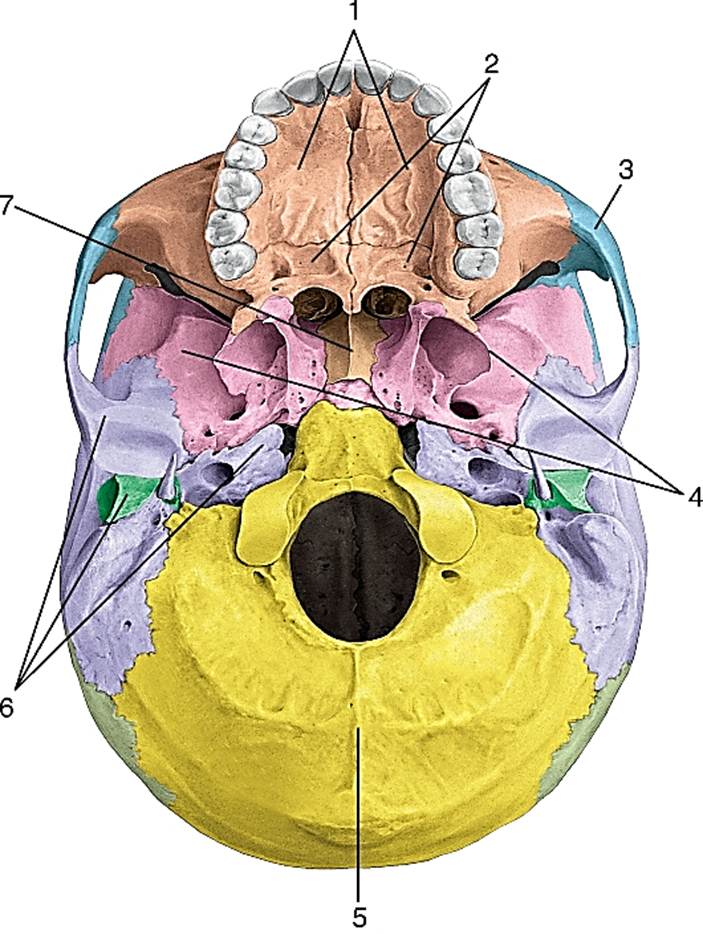

Анатомические детали: Фотографии топографии черепа с нижнего вида

Раздел: Альбом идей